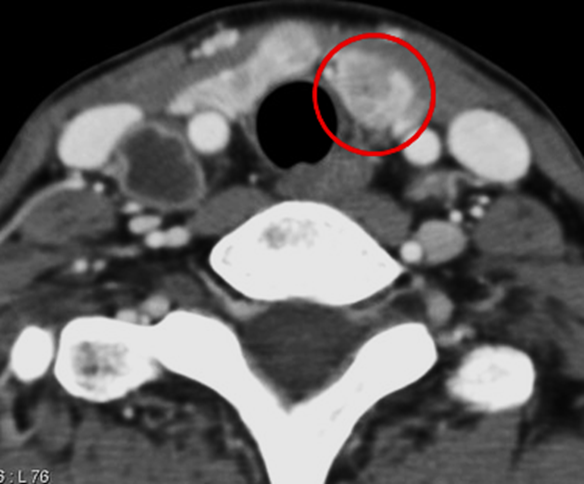

Contrast-enhanced CT images are shown below.

Which of the following is the most prominent finding on the chest CT scan?

(1) Right lower paratracheal mass with central necrosis

(2) Multiple bilateral pulmonary nodules

(3) Numerous pulmonary nodules in a random (miliary) distribution

(4) Large saddle embolus with multiple segmental and subsegmental emboli

(5) Both (1) and (2)

(6) Both (1) and (3)

(7) None of the above

Chest CT:

Multiple bilateral pulmonary metastases are present. A large mass arising from the right paratracheal thyroid region is observed, demonstrating central necrosis and mass effect, with leftward deviation of the trachea.